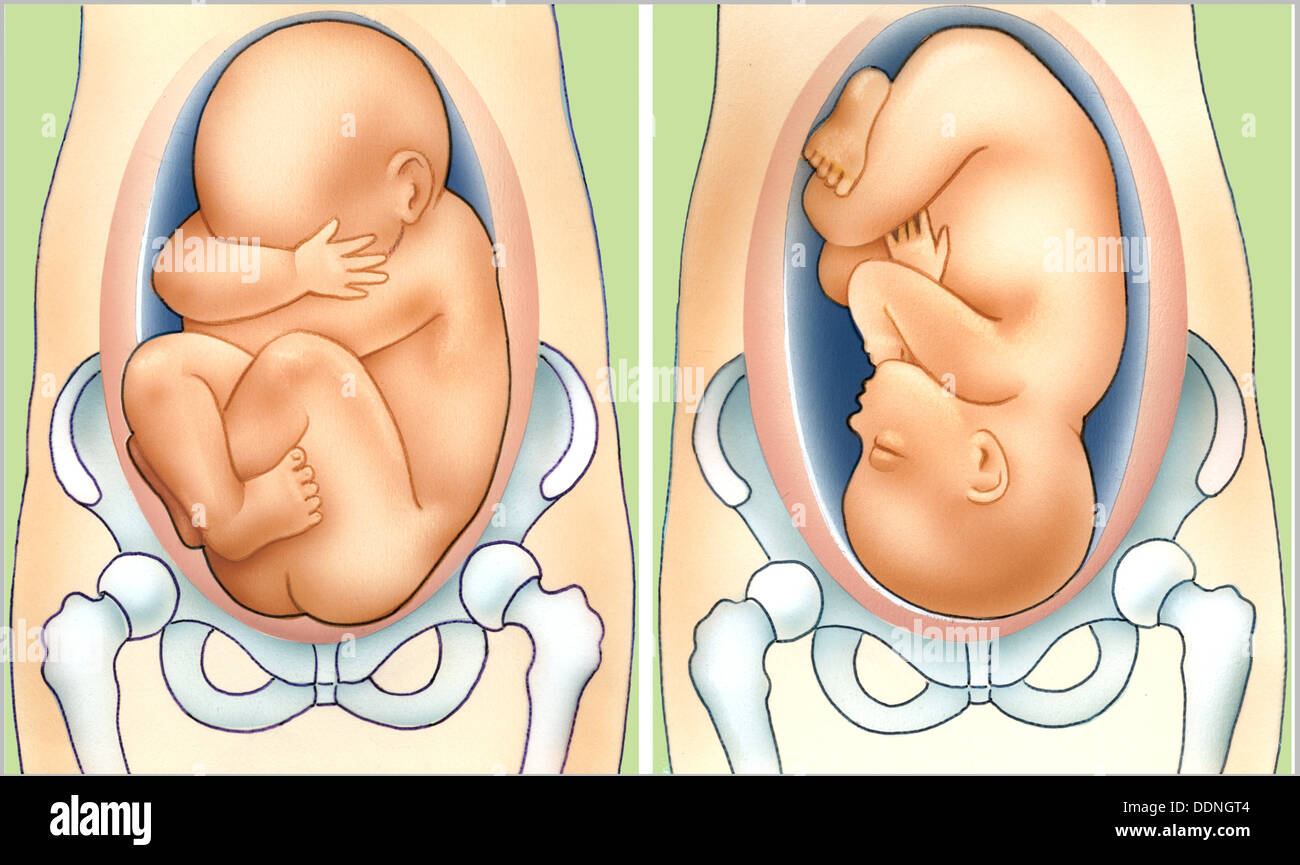

Во время беременности, положение плода имеет большое значение для мамы и малыша. Одним из типичных положений является продольное предлежание головное. В этом положении голова малыша находится внизу, а ножки - наверху. Это положение достаточно распространено и предпочтительно для естественных родов.

Плод лежит головой вниз

Ребенок вниз головой в животе

Плод лежит головой вниз